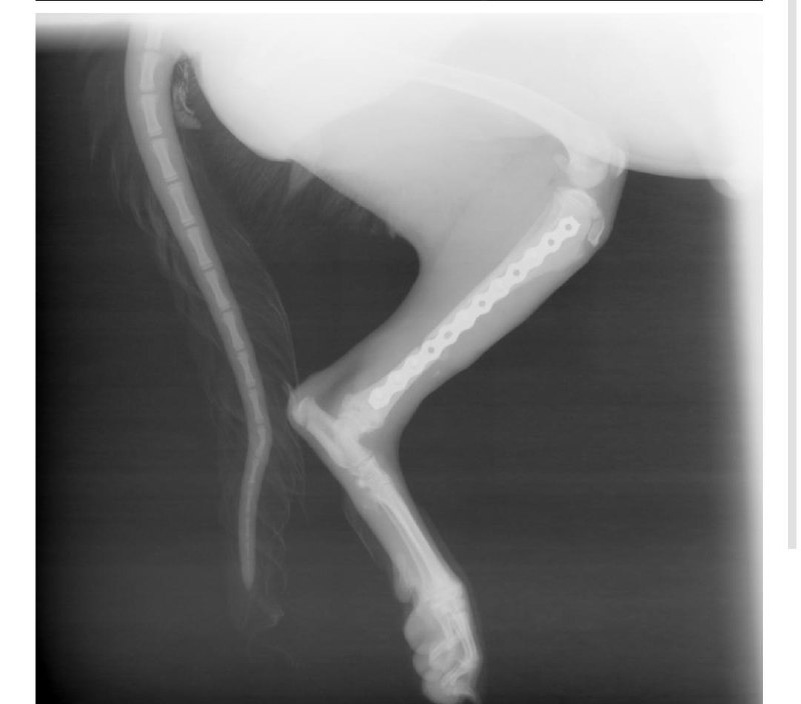

Щенку провели операцию. Поставили в лапку конструкцию 🙈 Если все будет хорошо, то она останется там навсегда. Все прошло хорошо. Несколько дней (чем больше тем лучше) девчонке надо пробыть в стационаре.

Долго ее держать возможности нет. Ну и идти ей, собственно, некуда.